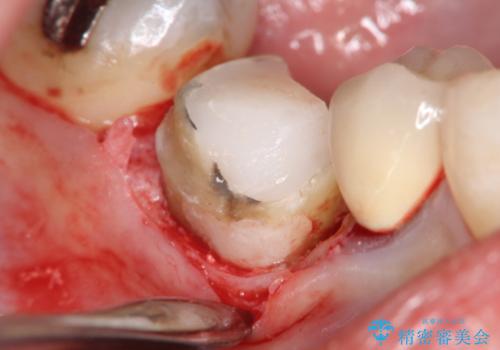

- 歯と歯の間で見つかりづらい虫歯でしたが、顕微鏡で確認し患者様に説明することで理解していただき、セラミックインレーにて修復治療を行いました。

劣化の少ないセラミックインレーを選んでいただき、色調にも満足していただきました。

当院でのセラミックインレーは必ずラバーダム防湿を行なって装着しております。